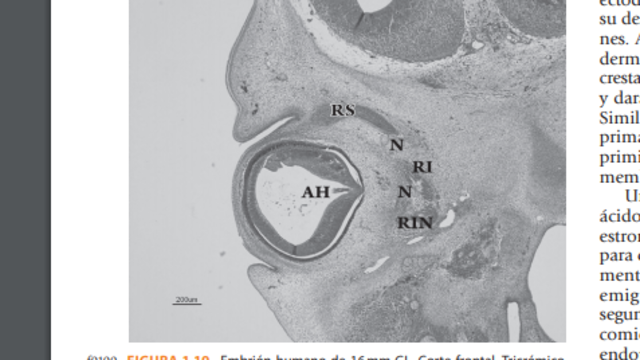

*El nervio óptico presenta un trayecto que va desde la parte posterior del globo ocular hasta el quiasma. Los glioblasto separan las fibras nerviosas en la región coroidea, forman una limitante en el trayecto infraorbitario, separándolo del mesénquima vecino.

*La porción orbitaria posterior del nervio óptico muestra la relación del nervio óptico con el futuro anillo del Zinn, así como con los músculos recto superior e interno. En el canal óptico se relaciona con la arteria oftálmica.